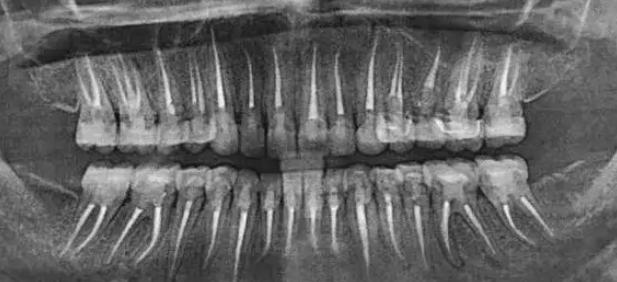

根管治疗常犯的五大错误操作,千万注意!